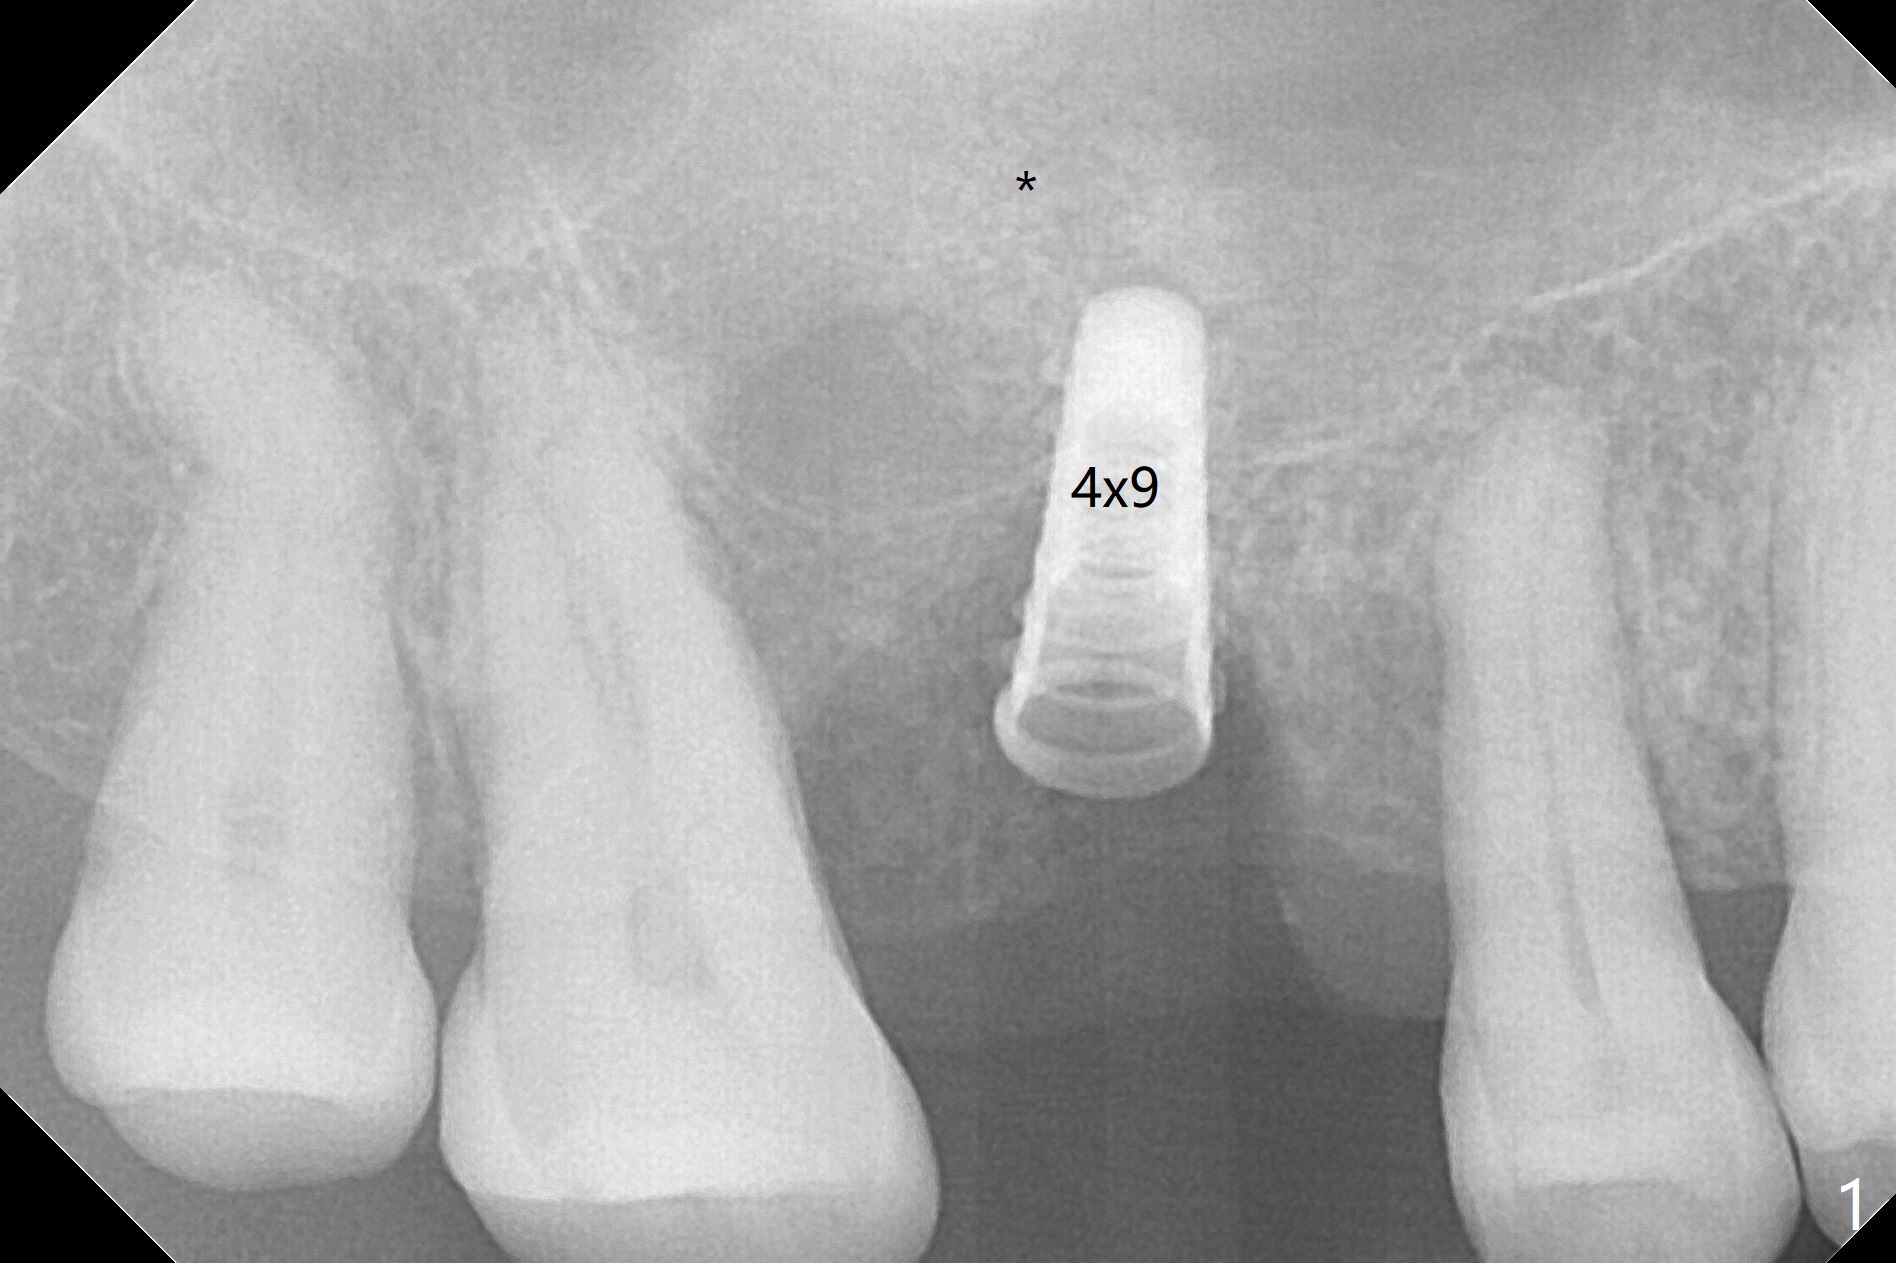

After extraction and debridement, osteotomy is initiated in the mesiobuccal socket free hand. Since the remaining bone is ~ 2 mm, the sinus floor is perforated suddenly. Fortunately the sinus membrane is not, as related to its thickening (similar to water ballooning, without symptom). Use 2-3.5 mm drills to enlarge the bony perforation (mainly lateral movement), followed by pushing bone graft upstairs with a curette (Fig.1 *); insert a 4x9 mm dummy implant (Fig.1) to determine the length of the final implant (Fig.2,3). A drawback of this case is the low torque (<20 Ncm), considering the thin bone. Following deeper implant placement, a 5.2x6(2) mm temporary abutment is placed for an immediate provisional to keep large amount of bone graft in place (Fig.3 *). There is no pain 1 week postop, while the immediate provisional remains stable partially because of the temporary abutment (Fig.4 ^). Four months postop, the temporary crown is loose. After removal of the temp and the temp abutment, gingival cuff is erythematous. A 6x4 mm healing abutment is placed. The bone graft (Fig.3 *) appears to have attached to the root of the neighboring tooth and the implant threads 7 months post op (COVID 19, Fig.5 arrowheads)). The bone graft appears to continue to merge with the neighboring root, bone and implant 10 months postop (2.5 months post cementation, Fig.6). The bone graft in the sinus seems to collapse and condense 10 months postop (Fig.7 *).